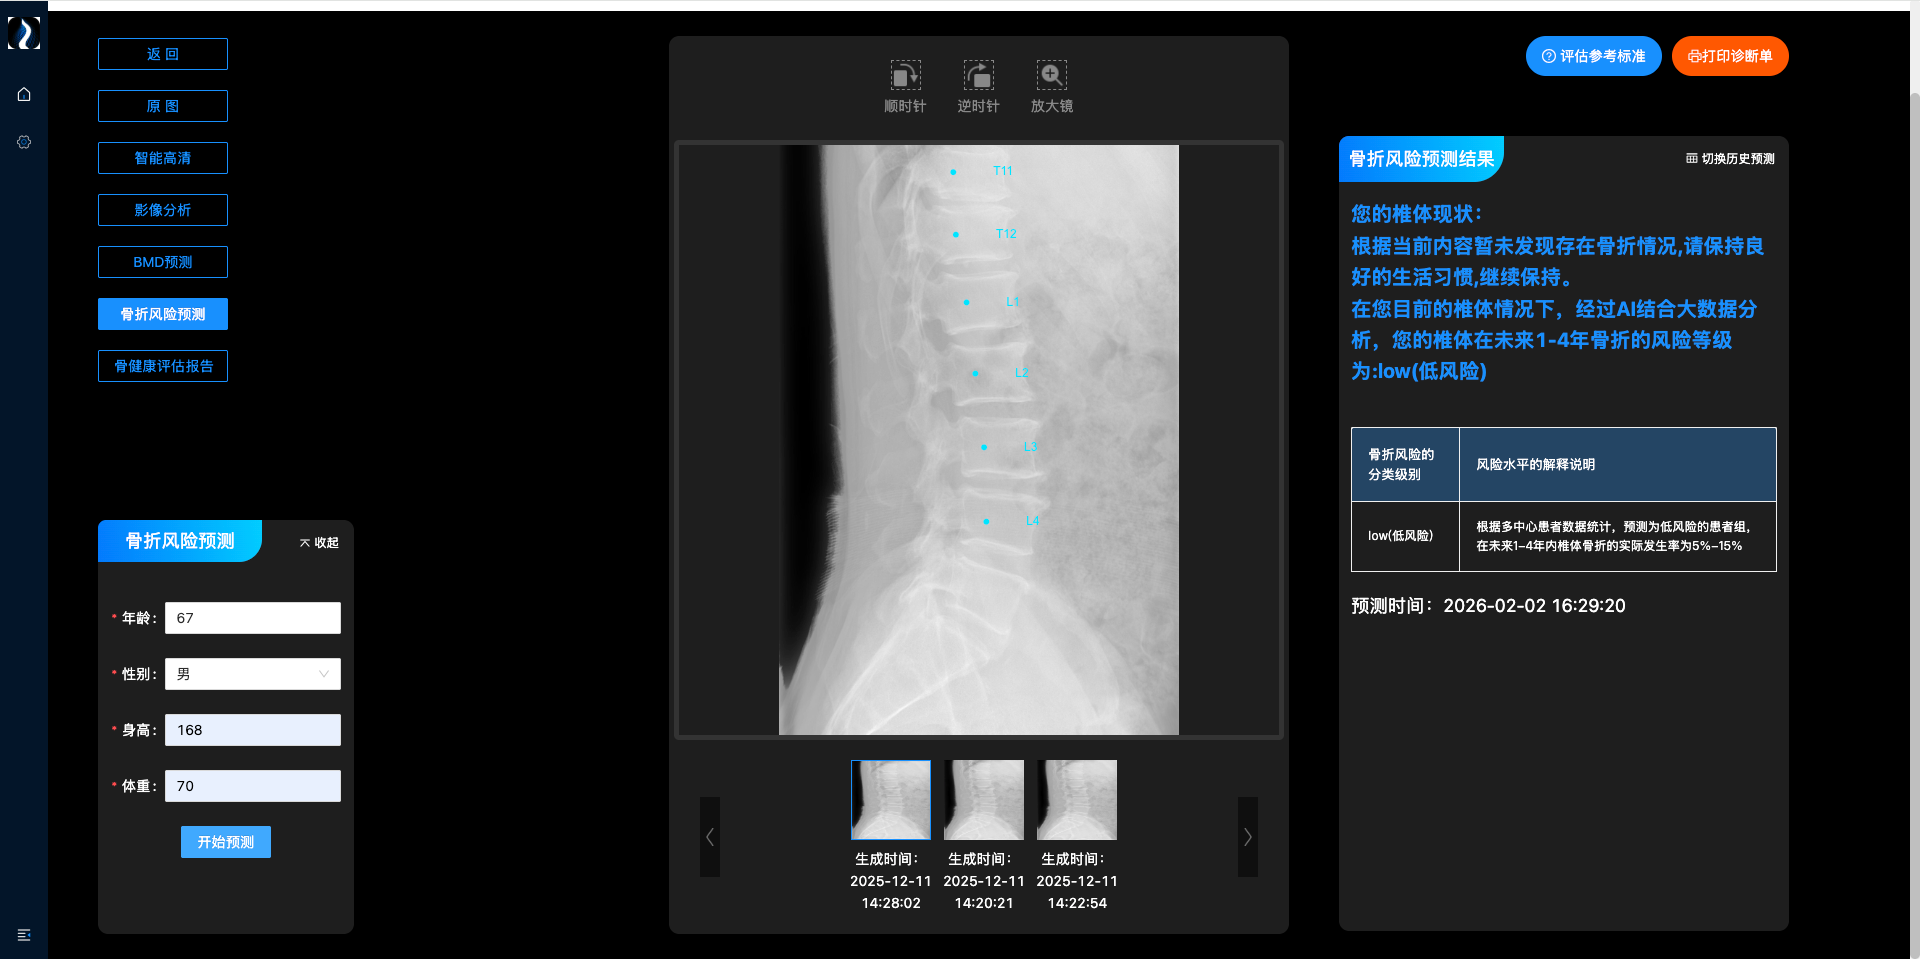

骨质疏松性椎体骨折预测系统

深度整合椎体影像及临床指标等多模态数据,通过智能算法精准评估个体骨折风险,为临床预防干预提供关键决策支持。